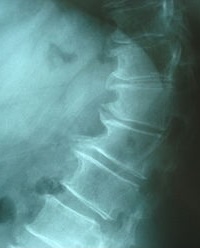

Cervical spondylosis

Harrygouvas at Greek Wikipedia · CC BY-SA 3.0 · source

Cervical spondylosis is a degenerative condition affecting the cervical portion of the spine associated with age-related changes in the intervertebral disc, facet joints and osteophyte formation. It commonly manifests with neck pain, radicular symptoms and, in severe cases, spinal cord compression leading to myelopathy, and is managed across specialties including neurology, orthopedics, rheumatology, physical therapy and sports medicine.

Diagnosis

Diagnosis is clinical supported by imaging modalities: plain radiography for alignment and osteophytes, computed tomography for osseous detail and magnetic resonance imaging for soft tissue and cord changes, used routinely at radiology services such as Mayo Clinic Radiology, Massachusetts General Hospital Radiology, Johns Hopkins Radiology, Karolinska Institutet and Royal College of Radiologists guidelines. Electrophysiological studies including nerve conduction studies and electromyography are performed in neurophysiology laboratories at Addenbrooke's Hospital, UCLH, Sheffield Teaching Hospitals and Bellevue Hospital to localize radiculopathy. Differential diagnosis requires exclusion of conditions managed by oncology centers (metastatic disease), infectious disease units (discitis), and rheumatology clinics (inflammatory spondyloarthropathies) in institutions like MD Anderson Cancer Center, CDC Emerging Infections Program, Hospital for Special Surgery and Brigham and Women's Hospital.